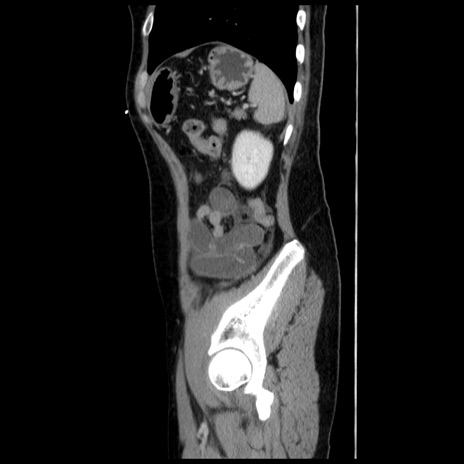

横断像

【症例】 50歳代女性

【主訴】 腹痛

【現病歴】前日生レバーを食べた。今朝に排便あり。 昼前に突然発症の腹痛を生じ、当院救急外来を受診した。

【既往歴】 子宮筋腫にてで子宮全摘後

【身体所見】 意識清明、腹部:平坦、軟、下腹部やや左を中心に圧痛・反跳痛あり、筋性防御あり

【データ】WBC 7800、CRP 0.07